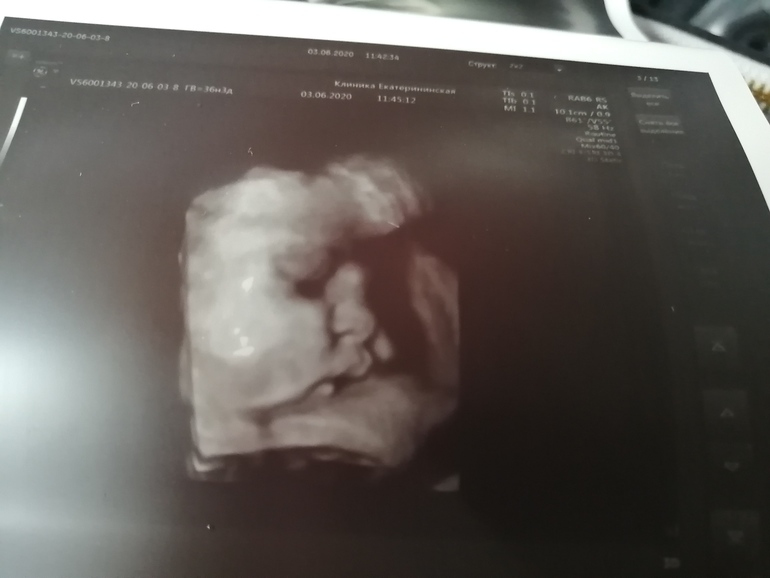

А вот наша крошка, уже с большими щечками🤗☺️❤️